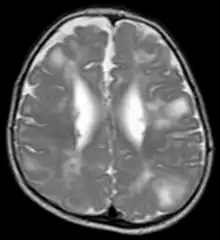

Classic intracranial manifestations of TSC include subependymal nodules and cortical/subcortical tubers.[12]

The tubers are typically triangular in configuration, with the apex pointed towards the ventricles, and are thought to represent foci of abnormal neuronal migration. The T2 signal abnormalities may subside in adulthood, but will still be visible on histopathological analysis. On magnetic resonance imaging (MRI), TSC patients can exhibit other signs consistent with abnormal neuron migration such as radial white matter tracts hyperintense on T2WI and heterotopic gray matter.

Subependymal nodules are composed of abnormal, swollen glial cells and bizarre multinucleated cells which are indeterminate for glial or neuronal origin. Interposed neural tissue is not present. These nodules have a tendency to calcify as the patient ages. A nodule that markedly enhances and enlarges over time should be considered suspicious for transformation into a subependymal giant cell astrocytoma, which typically develops in the region of the foramen of Monro, in which case it is at risk of developing an obstructive hydrocephalus.

A variable degree of ventricular enlargement is seen, either obstructive (e.g. by a subependymal nodule in the region of the foramen of Monro) or idiopathic in nature.